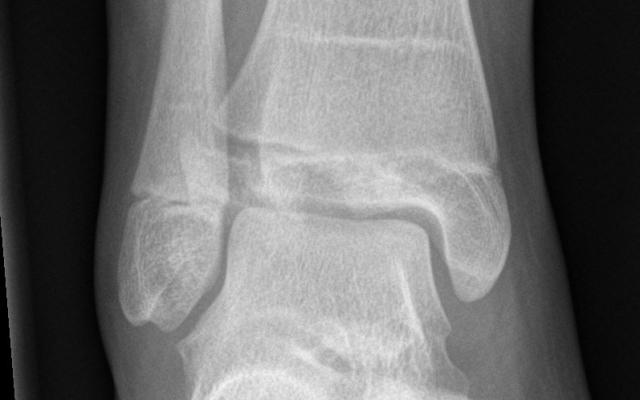

Dit artikel is alleen beschikbaar als PDF.Lees de PDF Artikelinformatie Online verschenen op 17 maart 1968 Citeer dit artikel als Ned Tijdschr Geneeskd. 1968;112:1271-2 Heb je nog vragen na het lezen van dit artikel? Check onze AI-tool en verbaas je over de antwoorden. ASK NTVG Ook interessant Beeldquiz Een tiener met enkelletsel Beeldquiz Een tiener met kniepijn Nieuws Barende tieners Meer gerelateerd … Reacties Login om een reactie te plaatsen